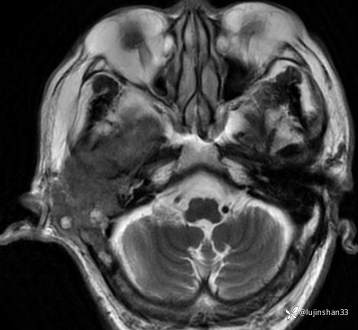

简要病史:患者2022年10月掏耳后出现右耳疼痛,流水,伴血性分泌物,伴听力下降,无头痛头晕,无口角歪斜,自行购买滴耳液及口服罗红霉素,效果不佳。后右耳痛加剧,偶需止疼药治疗。后于XXXXXX医院行中耳乳突CT检查示“右耳恶性肿瘤?坏死性外耳道炎?”颅脑磁共振平扫示“脑内多发缺血灶、梗塞灶,脑白质疏松,脑萎缩、右中耳恶性占位。”建议上级医院治疗。2023-4-13就诊于我科门诊,行右外耳道病理活检示“鳞状上皮黏膜慢性炎伴急性炎,可见较多炎性坏死,部分上皮增生明显伴不典型增生,小灶上皮呈重度异型增生伴癌变。”建议手术治疗。今患者为求进一步诊治,门诊以“颞骨占位(右)“收治入院。

MRI:

右侧颞骨鳞癌(T4)